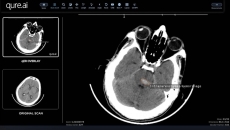

They will deploy AI to help reduce delays and gaps in stroke care management.